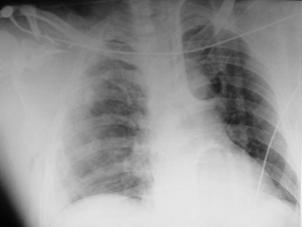

sufocant drept Pneumotorace

sufocant drept

Imagine

CT Imagine CT